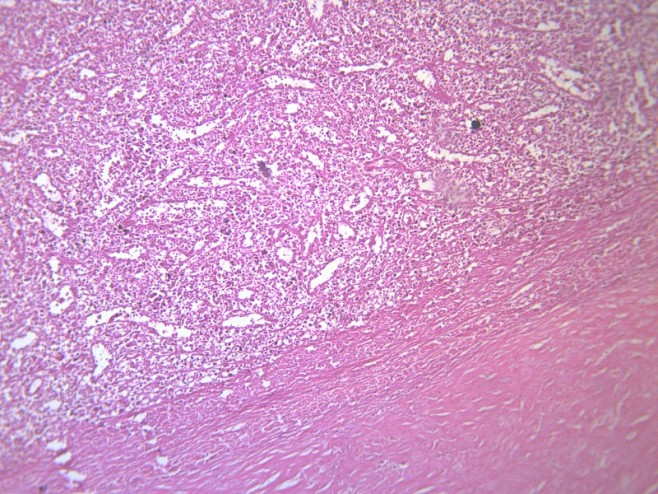

脾被膜玻璃样变显微切片图片

图片尺寸658x494

生物病理显微镜切片脾透明变性标本白底微距摄影

图片尺寸1200x800